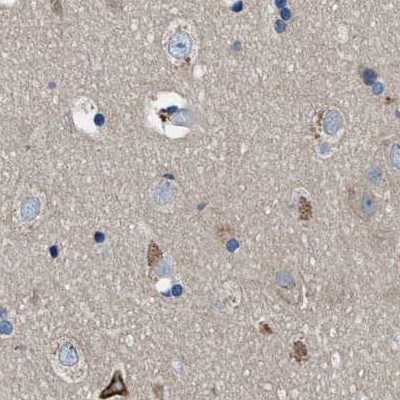

Immunohistochemical staining of human cerebral cortex, endometrium, fallopian tube and testis using Anti-PGR antibody HPA017176 (A) shows similar protein distribution across tissues to independent antibody HPA004751 (B).